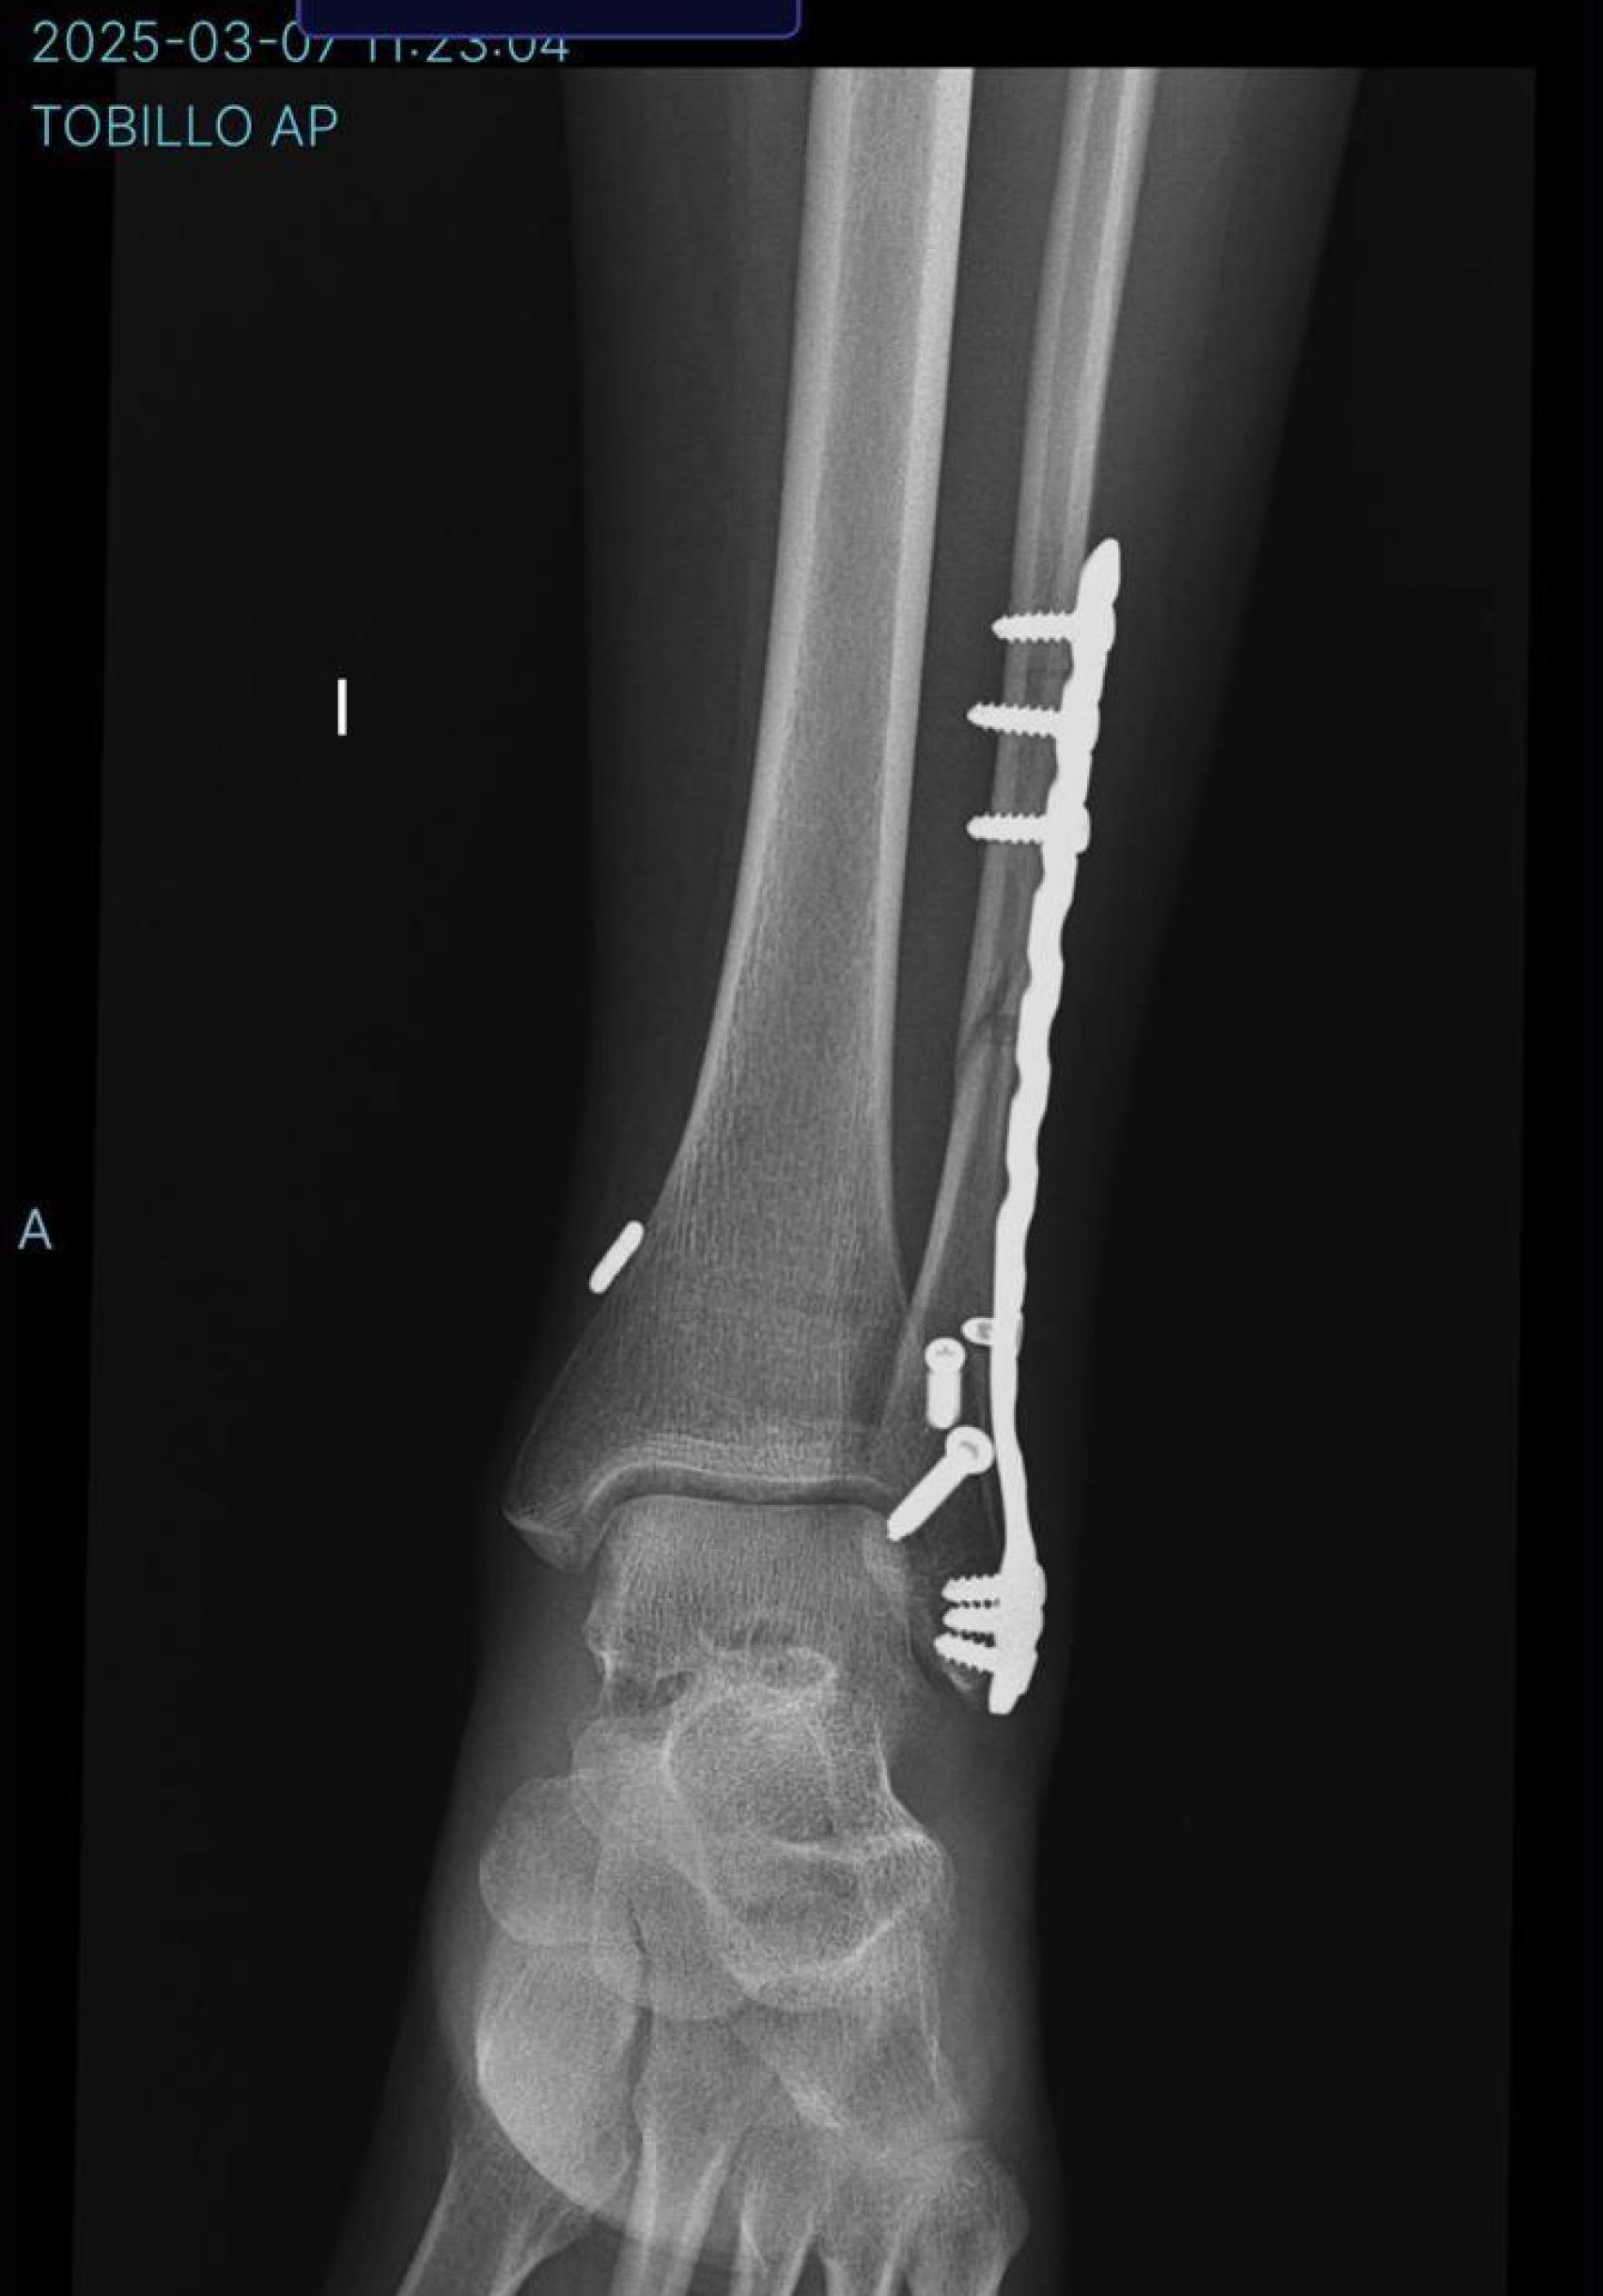

Radiografía tras la operación a la que se sometió Beatriz

Radiografía tras la operación a la que se sometió Beatriz CEDIDA